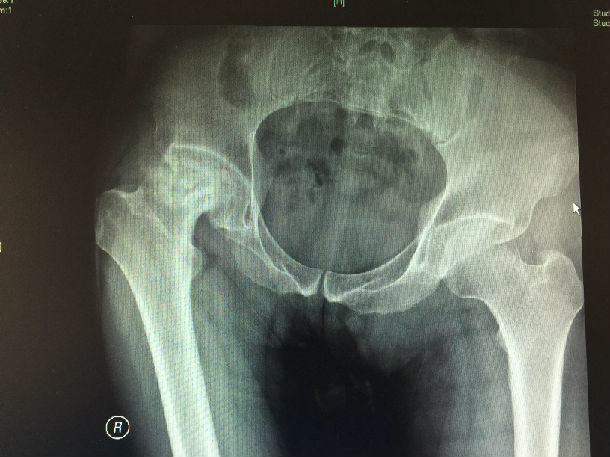

骨坏死。一名21岁男子髋关节的x光片显示骨坏

1280x1038 - 181KB - JPEG